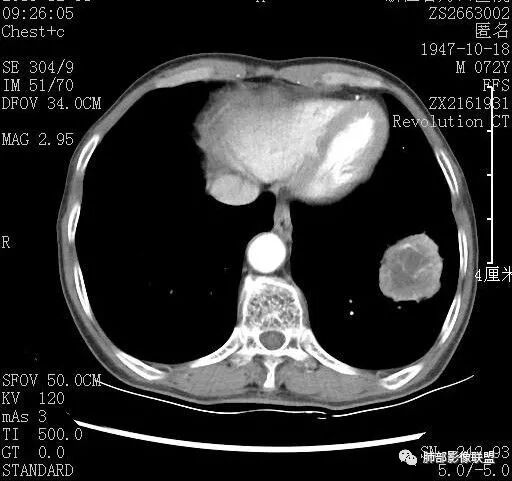

看纵隔窗及增强,内部无正常血管走行,支气管截断,偏心空洞,弥漫边界不清坏死,支持恶性,综合一下,癌(鳞?)>结核

右肺下叶肿块,分叶,近端支气管部分堵塞,部分沿壁厚,沼泽样强化,可见空洞,邻近胸膜少量积液,膈肌牵拉,考虑肿瘤,鳞癌?鉴别NTM

青年男性,慢性病程,右肺下叶团块影,形态不规则,内见空洞,壁厚薄不均,不均匀轻度强化。考虑恶性,肺癌,肿标中角蛋白19增高,倾向于鳞癌,鉴别结核。

中年男性,有咳嗽咳痰病史俩月,亚急性病程,炎性指标不高,右肺下叶后基底段近胸膜下不规则肿块,边缘膨隆毛糙,支气管近端阻塞,内有厚壁空洞,无液平,洞壁不均匀强化,周围支气管壁厚,远端有点片影,考虑鳞癌可能性大,鉴别肺脓肿和肺结核。但是血沉不快,crp不高,有点不大符合炎性。

看一下病灶主体,支气管堵塞

1.支气管截断

6增强后有很多坏死,与实性成分分界不清

7.脐凹?

密度:周围型鳞癌中心部多有空洞样改变和低密度区。压迫增殖型肿块坏死倾向强,预后差。见到肿块内中心广泛坏死、或散在坏死灶形成的低密度区,坏死边缘不清,常呈沼泽样坏死,术后生存率多在1年以内。周围型鳞癌营养血管受到浸润闭塞,引起坏死形成空洞(32.3%),在肺癌的各组织型中鳞癌空洞发生率最高。多为偏心性空洞(远离肺门一侧),少数病例为中心型空洞,单发或多发,可有气液面;肿块中央侧支气管大多数阻塞,无引流支气管,即使有引流支气管也不在中央侧; 与良性空洞不同的是有壁结节和存在洞壁最大厚度>15mm的部分。